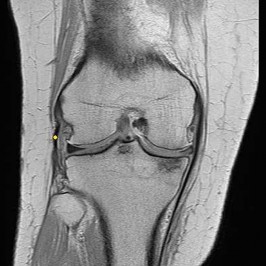

CLINICAL SITUATION FOR QUESTIONS 22 THROUGH 25

A 22-year-old man sustains an injury to his right knee in a motor vehicle collision. Figure 22a is the posterior stress radiograph of the involved knee, and Figure 22b is a selected MR image that identifies the injured structure.

Which relationship is noted for the structure identified by the arrow in Figure 22b? 24

- The anterolateral bundle is tensioned in mid flexion, and the posteromedial bundle is tensioned in both extension and high flexion.

The stress radiographs demonstrate posterior instability of the right knee in flexion. The MR images demonstrate injury to both the anterior and posterior cruciate ligament (PCL), with the stump identified with the arrow on the MR image (Figure 22b). The PCL has 2 functional bands. The anterolateral bundle originates from the roof of the intercondylar notch. It runs in a posterolateral direction onto the tibial crest between the posterior attachment of the medial and lateral menisci. During a double-bundled posterior ligament reconstruction, the

anterolateral bundle is tensioned with the knee in a position of mid flexion. The posteromedial bundle has a variable pattern of tension both in extension and in high flexion. Tensioning of the posteromedial bundle in extension may contribute to resistance against knee hyperextension.